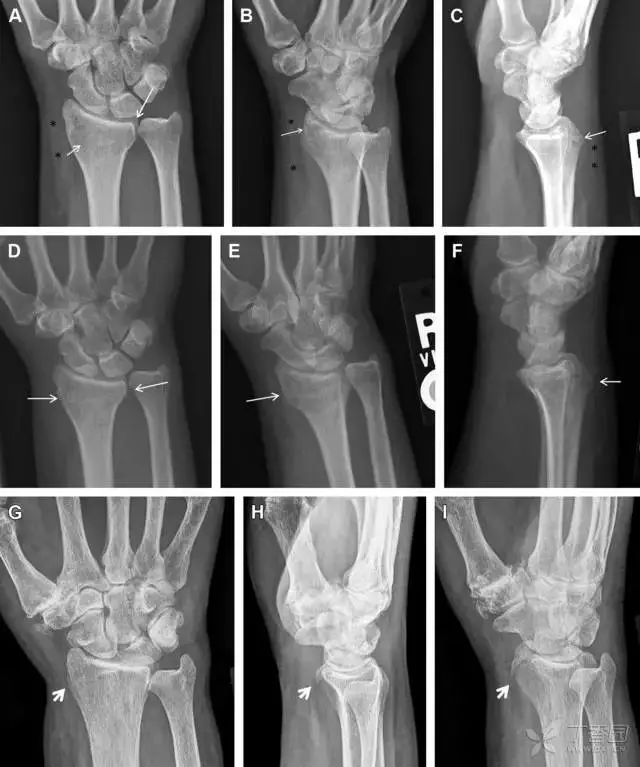

30桡骨远端骨折

常规进行前后位、侧位、斜位 X 线检查,对于大多数桡骨远端骨折来说不容易漏诊;但是对于无移位的骨折,特别是桡骨茎突骨折,容易漏诊。桡骨茎突骨折是一斜行的骨折,常累及关节面,常发生于轴向应力或直接打击。

图 1 57 岁女性,摔倒后手掌撑地,桡骨茎突压痛。(A~C)前后位、斜位、侧位片示软组织肿胀(*)和发丝样骨折(白色箭头);(D~F)2 周后,前后位、斜位、侧位片示骨折线显明,由于新骨痂沉积而呈现透亮线与硬化线并存;(G~I)另一患者,桡骨茎突骨折在前后位及侧位片上显示不明显,而在斜位片显示更清楚